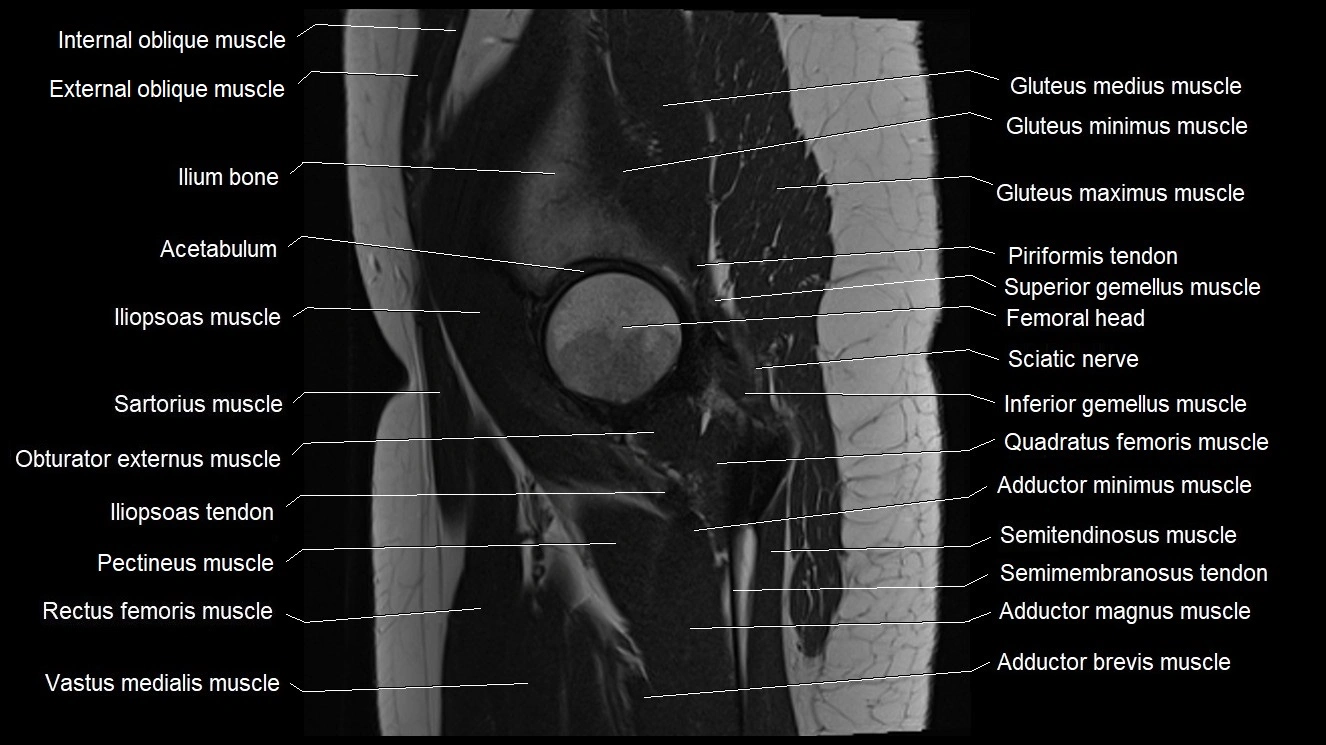

- Acetabulum

- Gluteus medius muscle

- Gluteus minimus muscle

- Gluteus maximus muscle

- Gluteus medius tendon

- Iliopsoas muscle

- Iliopsoas tendon

- Ilium bone

- Inferior gemellus muscle

- Inferior gluteal artery

- Obturator externus muscle

- Pectineus muscle

- Quadratus femoris muscle

- Rectus femoris muscle

- Sartorius muscle

- Semimembranosus tendon (proximal)

- Superior gemellus muscle

- Vastus intermedius muscle

- Vastus medialis muscle

- Adductor brevis muscle

- Adductor magnus muscle

- Adductor minimus muscle